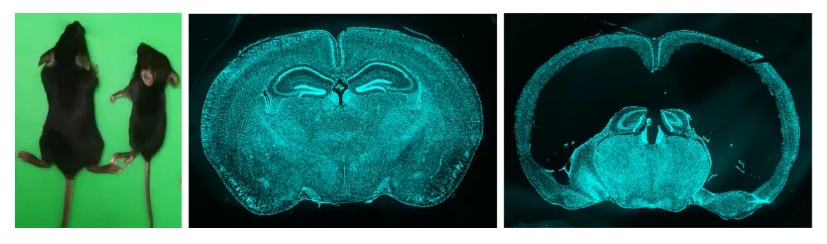

通过将Sspo-Cre和Sspo-CreER与DTA小鼠进行杂交,研究者们成功去除了子代小鼠的部分或者绝大部分SCO细胞。研究团队发现,当小鼠缺失SCO后,它们体型矮小,行动障碍,总体存活率很差。进一步发现,SCO缺陷小鼠的脑明显膨出,皮层很薄,局部皮层坍塌凹陷。脑切片显示,小鼠的脑室明显扩张,出现严重的大脑发育畸形。这些结果揭示SCO对大脑的生长发育是非常重要的,它是大脑生长发育不可或缺的一个重要器官(见图)。